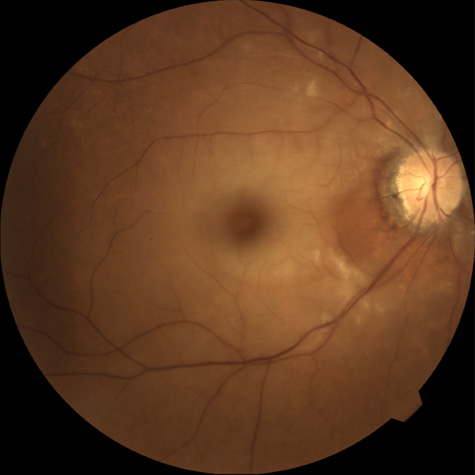

The patient describes either a sudden loss of vision if the branch retinal artery involves the macula or a visual field defect or both. Initial visual acuities can range from 20/15 to hand movements, but in one series, more than three-fourths of all patients had an initial visual acuity of 20/40 or better.94 Most patients who are seen with have branch retinal artery obstruction have unilateral obstructions, but about 8% later develop branch retinal artery obstruction in the opposite eye.94 Occasionally, patients present with a bilateral branch retinal artery obstruction.94 Some have obstructive retinal arteries without evidence of systemic abnormalities,95,96 whereas others have accompanying symptoms such as deafness.97,98 Some younger patients—usually women—have been reported to have an idiopathic syndrome of branch retinal artery obstruction, encephalopathy, and hearing loss (Susac syndrome).99–104,406 The eyes on these patients are characterized by significant systemic thromboembolic events; recurrent bilateral retinal arterial occlusions; segmental arteriolar staining by fluorescein angiography, occasionally associated with periarteriolar retinal whitening or mild vitreous cells; and a predilection for vestibuloauditory or transient sensorimotor symptoms.104 Some patients, however, present with only recurrent bilateral retinal arteriolar occlusions and never develop the associated vestibuloauditory or sensorimotor systems; whether these patients have a partial manifestation of Susac syndrome is unknown. The etiology of branch retinal artery obstruction in most cases is similar to that of central retinal artery obstruction (see Table 1). Retinal diseases (such as toxoplasmosis) can also cause branch retinal artery obstruction. Hasegawa and co-workers411 have reported on the multifocal electroretinogram in patients with a branch retinal vein occlusion. They found that both the first and second order multifocal electroretinogram amplitudes decreased in the effected area of the retina compared with the normal retina, but the second order multifocal electroretinogram was more affected by a branch retinal artery occlusion, suggesting that the second order multifocal electroretinogram is a more sensitive indicator of inner retinal dysfunction.411 The complications of branch retinal artery obstruction can include retinal neovascularization, although this is rare.105 When neovascularization develops, it may be related to decreased blood flow to the eye, such as that due to carotid artery disease106 or diabetes mellitus.107 Neovascularization has been reported as a sequel to obstructive retinal arteriolitis.95 Vitreous hemorrhage can occur after neovascularization.87,107 Occasionally, retinal breaks occur after branch retinal artery obstruction.108 Dutton and Craig109 treated a retinal embolus causing branch retinal artery occlusion with the argon laser after other therapy had failed; they were able to make the embolus break up and disappear but without improvement in visual function.109 Ciulla and colleagues,110 however, were able to only disrupt one retinal emboli out of four in a rabbit model of artery occlusion using human atherosclerotic material treated with the argon laser. They also failed to dislodge emboli in a human with branch retinal artery obstruction, and no clinical improvement resulted.110 Peyman and Gremillion111 removed a branch retinal artery embolus in a patient with branch retinal artery occlusion using a 30-gauge needle and a pars plana vitrectomy; the patient regained vision to 20/200. Most clinicians do not treat branch retinal artery obstruction, and there are no published clinical trials that suggest any treatment is better in terms of a final visual result than no treatment at all. An investigation into associated systemic abnormalities is important, and treatment of any systemic abnormalities that may be found is necessary in most cases. In those patients who present with retinal neovascularization, the treatment of choice is scatter photocoagulation delivered to the area of ischemic retina, with delivery similar to that used for neovascularization secondary to branch retinal vein obstruction.106,112 CILIORETINAL ARTERY OBSTRUCTION Cilioretinal arteries can be selectively obstructed (Fig. 3). More commonly, however, they occur in association with central retinal vein obstruction.113 When they supply a significant portion of the macula, decreased visual acuity is common. Prognosis for visual outcome in such patients is good. Brown and co-workers114 studied 10 eyes having an isolated cilioretinal artery obstruction. Of those, 60% had an initial visual acuity of 20/40 or better and on follow-up examination, all eyes but one had a best-corrected visual acuity of 20/40 or better.114